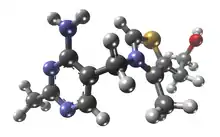

Síndrome de Wernicke-Korsakoff é uma combinação da encefalopatia de Wernicke, causada pela deficiência severa de tiamina (vitamina B1), com a psicose de Korsakoff, uma sequela neurológica de encefalopatia de Wernicke crônica. A forma metabolicamente ativa da tiamina é o pirofosfato de tiamina, que desempenha um papel importante como um co-fator como coenzima no metabolismo da glicose. As enzimas que são dependentes de pirofosfato de tiamina estão associadas com o ciclo do ácido cítrico (também conhecido como ciclo de Krebs), que catalisam a oxidação do piruvato, α-cetoglutarato e aminoácidos de cadeia ramificada. Assim, qualquer coisa que estimular o metabolismo da glicose vai agravar essa deficiência de tiamina clínica ou sub-clínica existente.